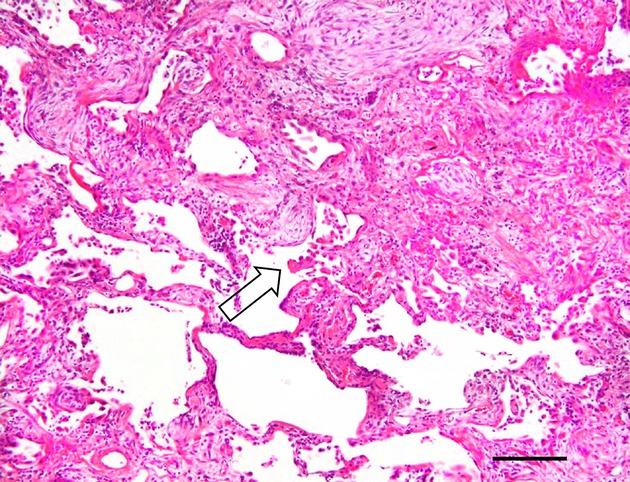

Pneumocyte injury is a characteristic of pulmonary interstitial pneumonias (IPs). Histological markers of pneumocyte injury and inflammation include pneumocyte necrosis, erosion, hyaline membrane and fibrin exudation with subsequent intraluminal granulation tissue formation. We found that intracytoplasmic inclusions in pneumocytes are ubiquitin-positive (Ub(+) ) and that the number of Ub(+) pneumocytes shows positive correlation with the extent of diffuse alveolar damage (DAD). To determine the role of Ub(+) pneumocytes and inclusions in IPs, we studied their relationship with pathological and clinical features of DAD, usual interstitial pneumonia (UIP) and organizing pneumonia (OP), including airspace enlargement with fibrosis (AEF). We analysed Ub(+) pneumocytes, inclusions, erosions and intraluminal granulation tissue in relation to pneumocyte injury. The numbers of immunohistochemically identified Ub(+) inclusions in each IP were higher than the number of inclusions detected by light microscopy. The inclusions detected by Ub(+) immunostaining were identical to the inclusions observed by light microscopy. UIP and DAD had many Ub(+) inclusions, while OP and AEF had fewer Ub(+) inclusions. These results suggest that the extent of Ub(+) inclusions reflects the severity of pneumocyte injury among IPs. Thus, Ub(+) inclusions are a histological marker of pneumocyte injury that may be helpful in determining the severity and prognosis of IPs.

肺细胞损伤是肺间质性肺炎(IPs)的一个特征。肺细胞损伤和炎症的组织学标志物包括肺细胞坏死、糜烂、透明膜和纤维蛋白渗出,随后形成管腔内肉芽组织。我们发现肺细胞内的包涵体是泛素阳性(Ub(+)),并且Ub(+)肺细胞的数量与弥漫性肺泡损伤(DAD)的程度呈正相关。为了确定Ub(+)肺细胞和包涵体在IPs中的作用,我们研究了它们与DAD、普通间质性肺炎(UIP)和机化性肺炎(OP)的病理和临床特征的关系,包括伴有纤维化的气腔扩大(AEF)。我们分析了与肺细胞损伤相关的Ub(+)肺细胞、包涵体、糜烂和管腔内肉芽组织。每个IP中免疫组化鉴定的Ub(+)包涵体数量高于光学显微镜检测到的包涵体数量。通过Ub(+)免疫染色检测到的包涵体与光学显微镜观察到的包涵体相同。UIP和DAD有许多Ub(+)包涵体,而OP和AEF的Ub(+)包涵体较少。这些结果表明,Ub(+)包涵体的程度反映了IPs中肺细胞损伤的严重程度。因此,Ub(+)包涵体是肺细胞损伤的组织学标志物,可能有助于确定IPs的严重程度和预后。